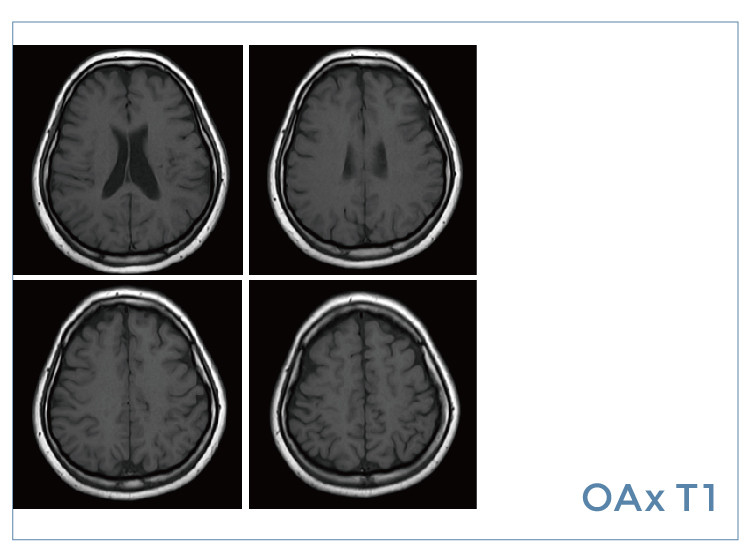

【朗润影像档案】20190823磁共振影像病例结果讨论